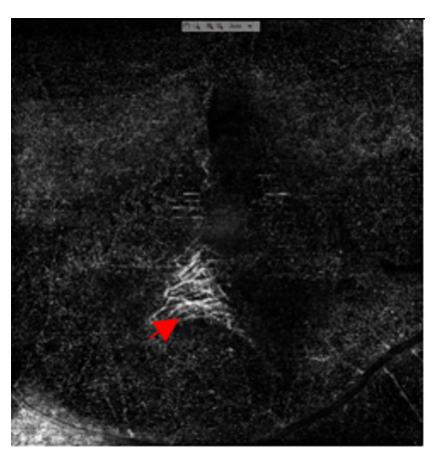

1 病例资料

患者,男, 16岁,体校学生,汉族,因“右眼眼前黑影遮挡,伴视力下降 2 周”为主诉入院。 2周前无明显诱因出现右眼眼前黑影遮挡,伴视力下降,不伴眼红、眼痛、畏光、流泪等症状。既往体健,生命征平稳,心肺腹未发现明显异常。眼部情况:右眼视力0.02, -3.00DS/ -1.25DC*171=0.25,左眼戴镜视力0.4, -1.75DS/ -1.50DC*9=1.0,双眼眼前节情况可,左眼眼底大致正常。右眼眼底及辅助检查(图1~6):黄斑区见一不连续弧形黄白色病灶,其周围见类圆形出血性神经上皮脱离(图1)。自发荧光显示黄斑区多个弧形呈低荧光病灶,黄斑去血性神经上皮脱离,部分因血自发荧光增强(图2)。行光学相干断层扫描血流成像(optical coherence tomography angiography,OCTA)检查,在视网膜无血管层可见弧形低密度区及网状CNV结构(图3),在脉络膜毛细血管层见经过黄斑中央脉络膜毛细血管弧形缺损区,暴露其下脉络膜中层血管(图4)。行荧光素钠造影(fluorescein angiography,FA)联合吲哚菁绿造影(indocyanine green angiography,ICGA)检查,ICGA见经过黄斑中心凹处一新月形弱荧光,视盘颞侧见多处小弧形弱荧光,均为脉络膜破裂部位。破裂病灶对应线扫光学相关断层扫描(optical coherence tomography,OCT)图RPE-Bruch膜复合体及脉络膜毛细血管断裂处,凹陷处见中高反射瘢痕信号,FA可见弧形染色并且中央有楔形荧光渗漏,考虑有脉络膜新生血管(choroidal neovascularization,CNV)形成可能(图5)。诊断:右眼多发性脉络膜破裂并CNV形成、黄斑视网膜下出血、双眼屈光不正。治疗上予玻璃体腔注射抗血管内皮生长因子(vascular endothelial growth factor,VEGF)治疗后1个月随访,视网膜下出血吸收,矫正视力提高到0.6(图6)。

20230131163804_2757.png

图3 OCTA黄斑区无血管层见两处弧形低密度区及网状CNV结构(箭头)

Figure 3 In the vascularized layer of OCTA macular area, there were two curved low density areas and reticular CNV structure (arrow)